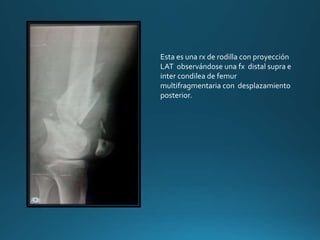

Esta es una rx de rodilla con proyección

LAT observándose una fx distal supra e

inter condilea de femur

multifragmentaria con desplazamiento

posterior.